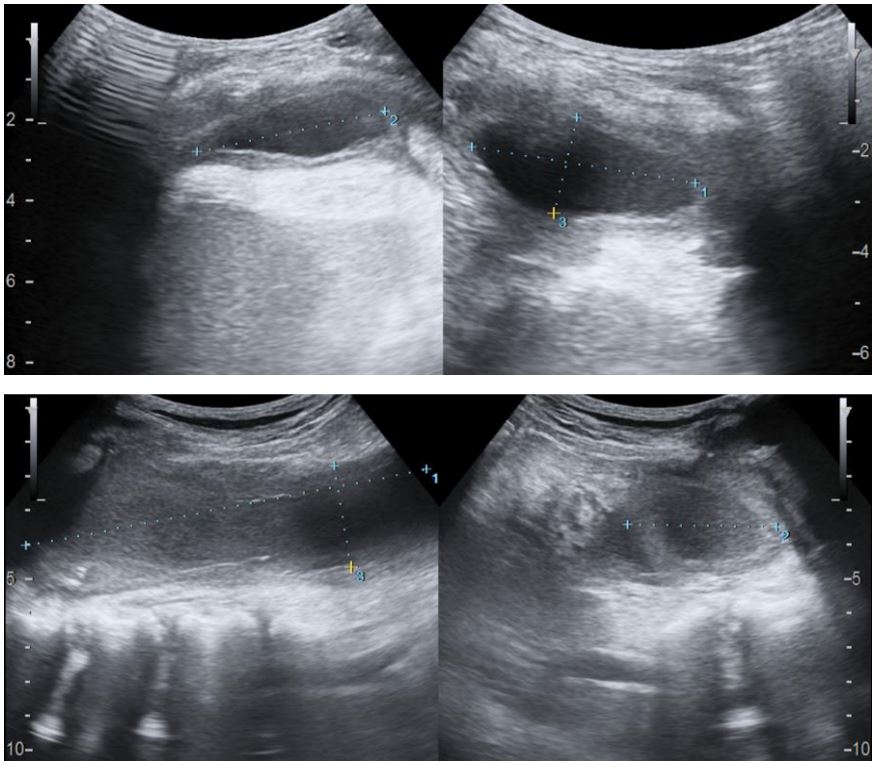

Figure 2: Chest ultrasound showing left empyema (A) and left psoas abscesses (B) with margins demarcated by calipers.

We present a case of P.M. An 11-year-old who initially presented with a three-week history of cough, Intermittent fever, and dyspnea. The initial diagnosis of left congenital diaphragmatic hernia was suspected from the chest radiograph and ultrasound in another institution as an opacified left hemithorax and bowel loops within the left thoracic cavity were found, respectively. The patient was subsequently referred to our institution where chest radiograph (Figure 1), chest ultrasound (Figure 2) and contrast-enhanced CT scan of the chest and upper abdomen (Figure 3-7) were done showing left perinephric and left psoas abscesses with intra-thoracic extension, probably through a left diaphragmatic defect, forming empyema thoracis and empyema necessitans. Culture of abscess fluid yielded no bacterial growth but GenExpert test was positive for M. tuberculosis.